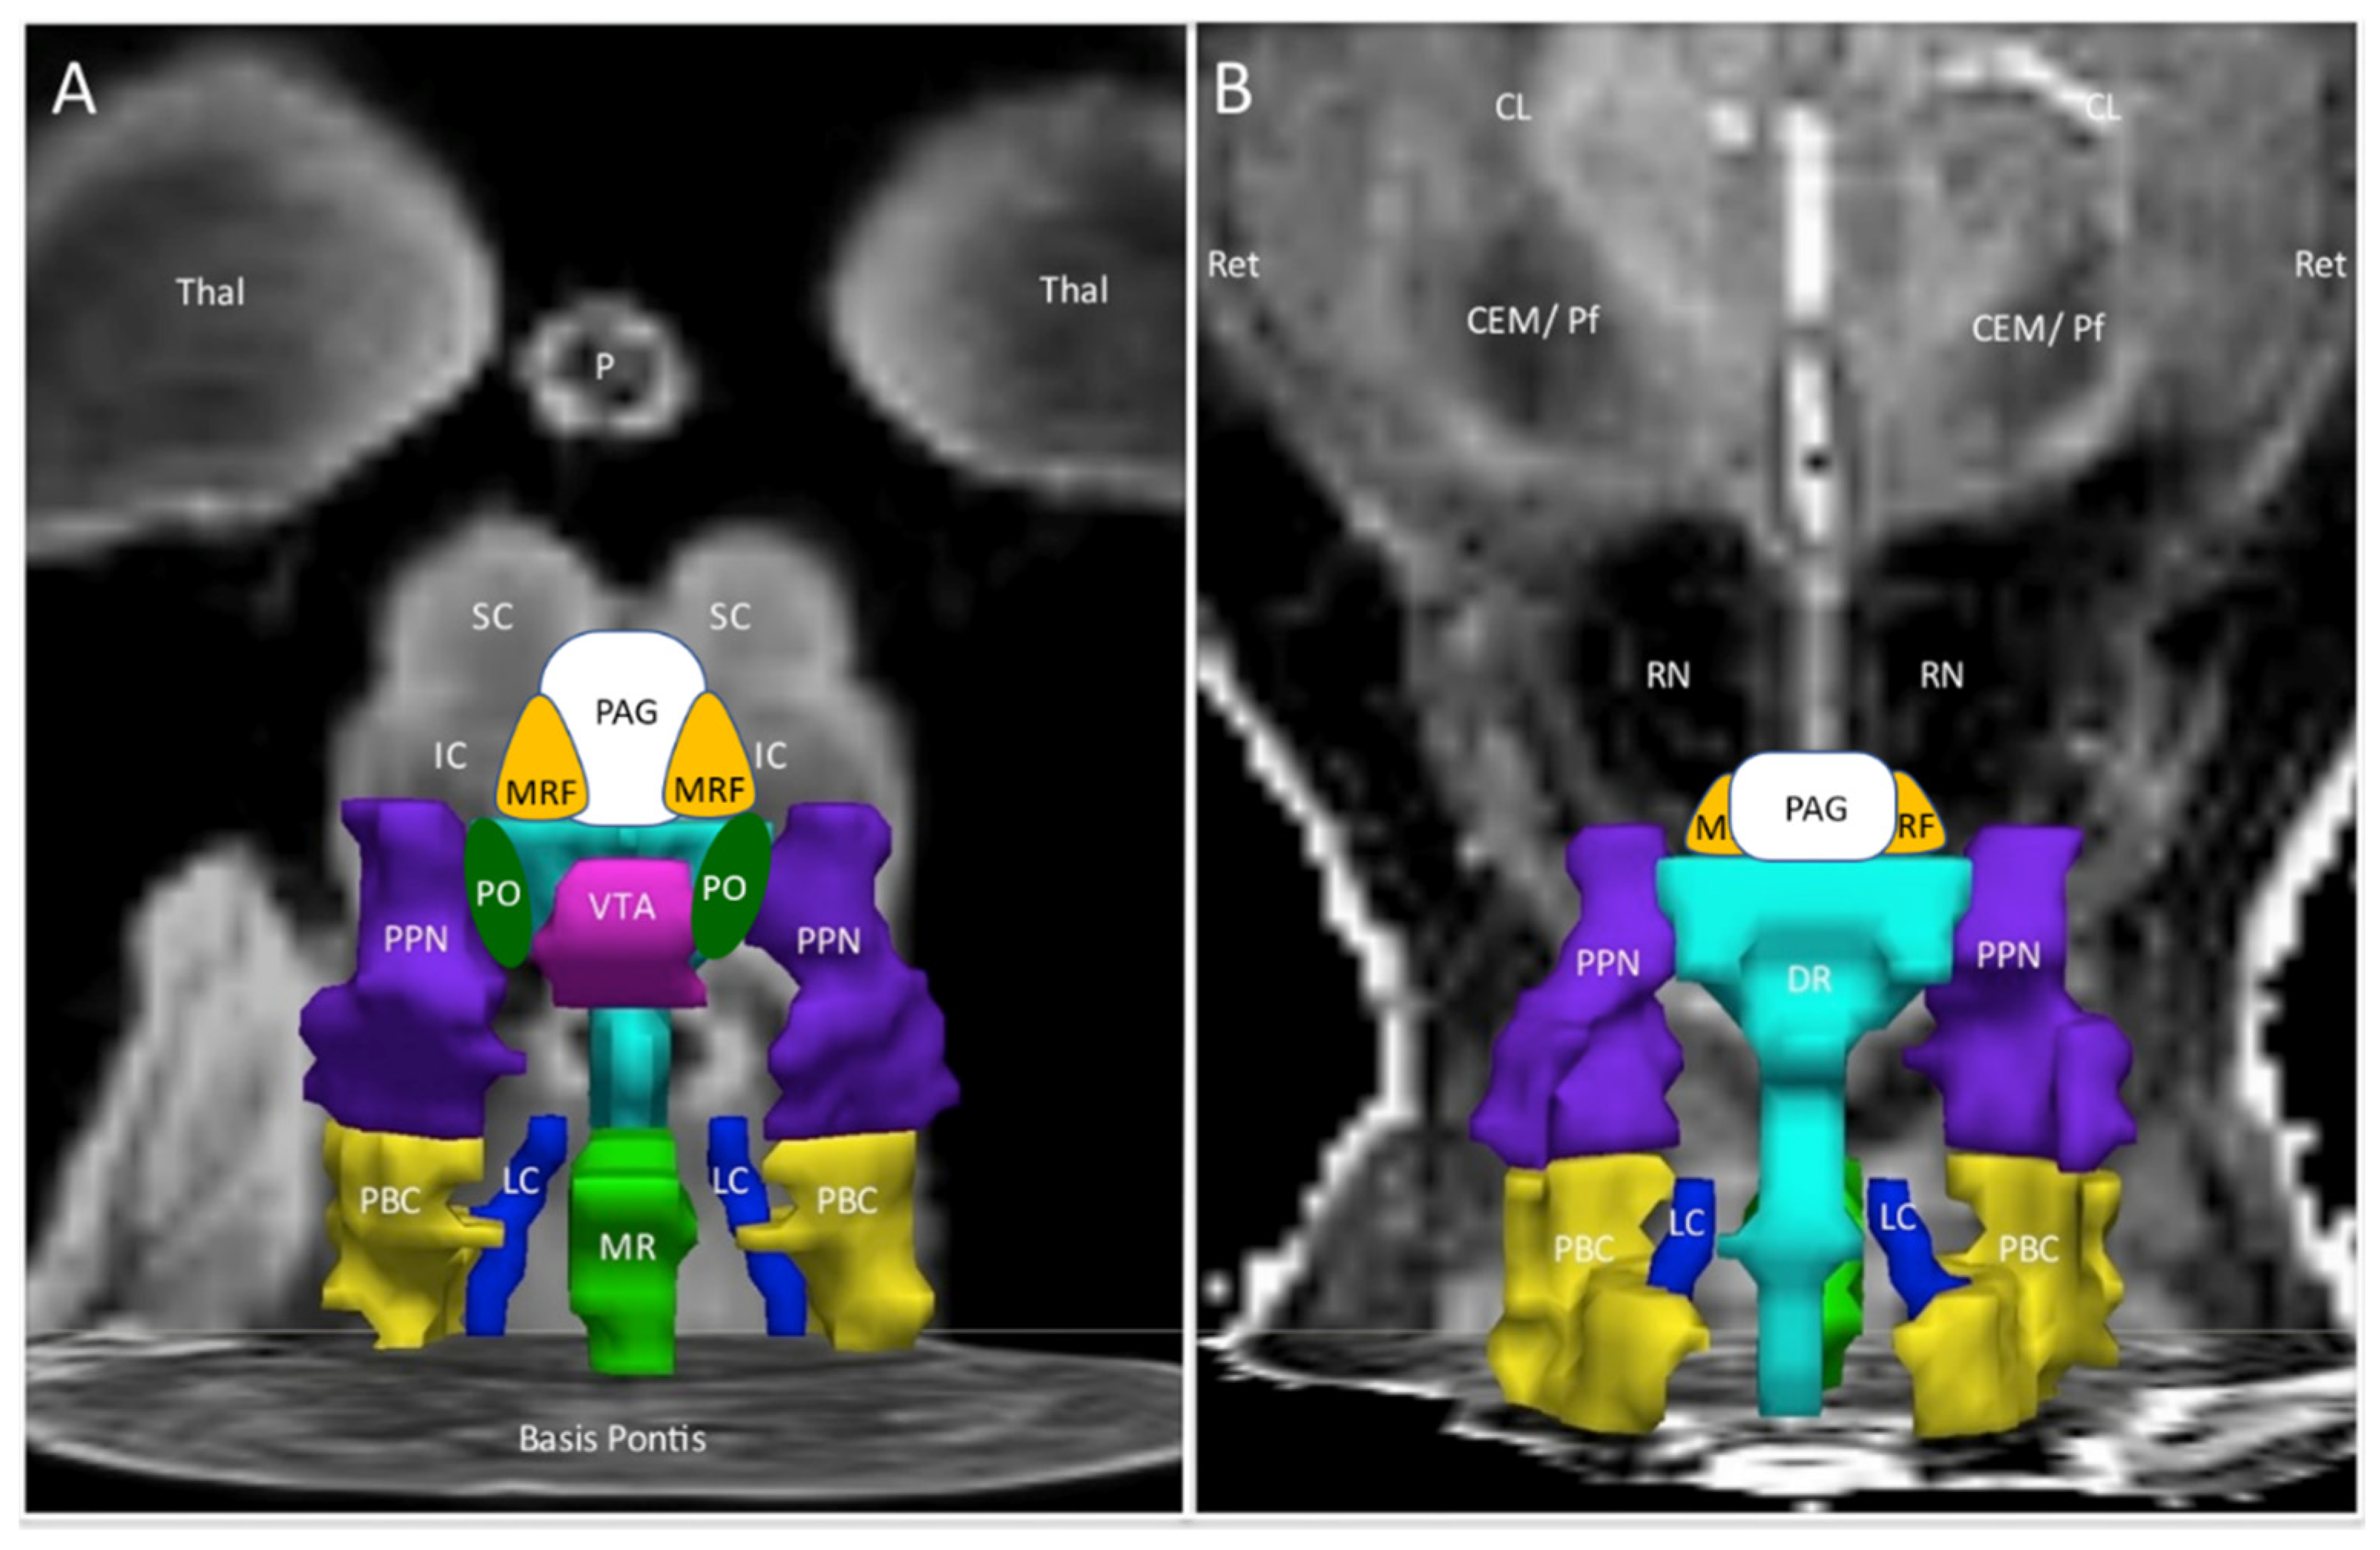

Figure 1.

Ascending arousal network. The original figure [37] in the coronal plane was annotated by adding periaqueductal grey (PAG, white), midbrain reticular formation (MRF, orange), and pontis oralis (PO, dark green). (A) The anterior view showed the ventral midbrain with posterior thalamus (Thal) as a “ceiling”, the superior (SC) and inferior colliculi (IC) as the backdrop, and Basis Pontis as the “floor”. (B) The posterior view of the dorsal midbrain was oriented to show the plane of the centromedian/parafascicular nucleus (CEM/Pf), reticular nucleus (Ret), and central lateral nucleus (CL) of the thalamus, pineal (P), and midbrain red nuclei (RN). This depiction suggested three layers with the MRF and PAG being most rostral. The middle layer contained the ventral tegmental area (VTA, violet), bilateral pontis oralis (PO, dark green), and pedunculotegmental nuclei (L and R PTN, formerly pedunculopontine nuclei and labeled PPN in the original image, navy blue) and dorsal raphe (DR, cyan) in the posterior midline. The caudal layer had median raphe (MR, green) and DR flanked by bilateral locus coeruleus (LC, navy blue) and parabrachial complex (PBC, yellow). The nuclei are contorted around white matter tracts that were not part of the original region of interest but constitute much of the ventral midbrain. The orientations of the nuclei displayed here do not align perfectly with the Paxinos histological atlas of the human brainstem [38].

Significant differences in activation of the midbrain nuclei in the ascending arousal network (Figure 1 and Figure 2) have special implications for pain, negative emotion, and neurobehavioural dysfunction in ME/CFS and GWI [42]. Great advances have been made in learning the functions of this vital yet underappreciated organ. A review of each nuclear region provides a fresh perspective for interpreting the current results and generating new hypotheses for postexertional malaise, ME/CFS, and GWI.